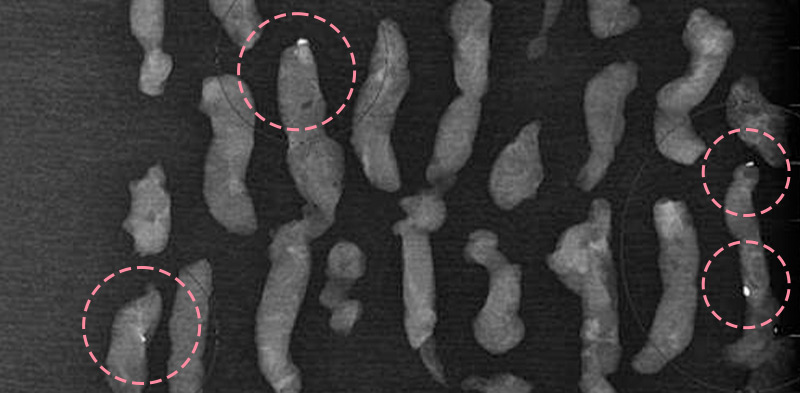

맘모톰시술 후 병리조직검사에서 상피내암(조기유방암)으로 진단되어 대학병원으로 연계해 드린 환자분의 사례입니다. 암을 초기 단계에 찾음으로써 항암치료 없이 간단한 수술을 통해 치료가 가능하였습니다.